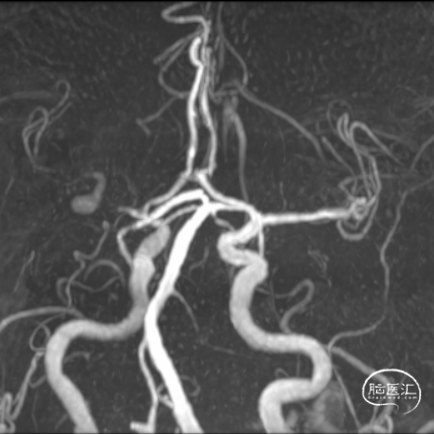

右侧大脑中动脉瘤合并近端狭窄的介入治疗

动脉粥样硬化性颅内动脉狭窄与颅内动脉瘤共存研究(CAIASA研究)表明,未破裂颅内动脉瘤患者中的颅内动脉粥样硬化性狭窄(ICAS)的总患病率为6.2%,并随着年龄增加。针对动脉瘤合并动脉狭窄的治疗根据治疗顺序不同,可以归纳为:优先颅内动脉狭窄的治疗、优先颅内动脉瘤的治疗以及同期治疗。本次将汇报一例右侧大脑中动脉瘤合并近端狭窄同期介入治疗及术后随访的病例。

The Coexistence of Atherosclerotic Intracranial Artery Stenosis and Intracranial Aneurysm (CAIASA) study indicates that the overall prevalence of intracranial atherosclerotic stenosis (ICAS) in patients with unruptured intracranial aneurysms is 6.2%, and it increases with age. Treatment strategies for aneurysms combined with arterial stenosis can be categorized based on the order of treatment: prioritizing intracranial arterial stenosis, prioritizing intracranial aneurysms, or simultaneous treatment. This report presents a case of simultaneous endovascular intervention for a right middle cerebral artery aneurysm with proximal stenosis and postoperative follow-up.

在临床实践中,未破裂颅内动脉瘤合并颅内外动脉狭窄的情况越发多见。动脉粥样硬化性颅内动脉狭窄与颅内动脉瘤共存研究(CAIASA研究)表明,未破裂颅内动脉瘤患者中的颅内动脉粥样硬化性狭窄(ICAS)的总患病率为6.2%,并随着年龄的增加,从1.4%(<40岁)增加到10.4%(60-70岁)。患病率的地区与年龄分布,表明我国老年人相较于人群总体可能有更大的疾病负担。

本次将汇报一例右侧大脑中动脉瘤合并近端狭窄同期介入治疗及术后随访的病例。

诊断:1.右侧大脑中动脉狭窄;2.右侧大脑中动脉瘤;3.高血压;4.右侧基底节区脑梗死。

术前影像学资料(DSA)